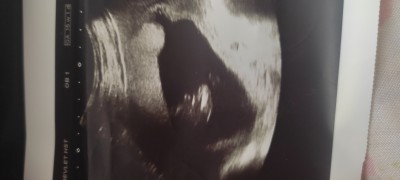

15. Haftada doktor böyle bir görüntü verdi bebeğin pipisi diye ama değişirmi yoksa kordonla karıştırmış olabilir miemin olamadım kesin dedi

Gebelik haftası 16